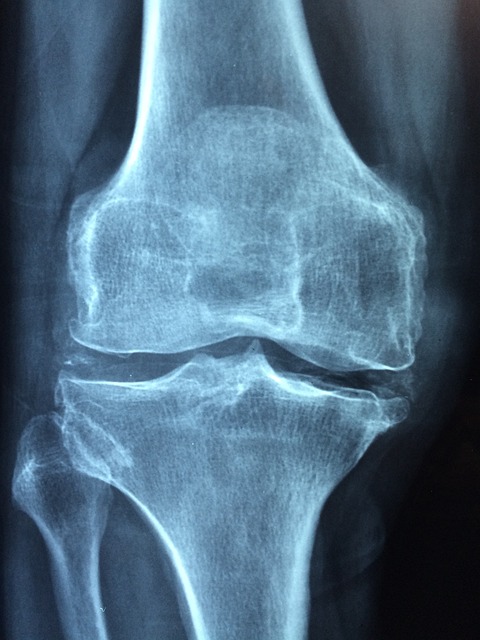

무릎 관절은 매일 체중의 3~5배 하중을 견디는 부위입니다.

러닝할 때는 착지 순간 체중의 7배까지 충격이 전달됩니다.

과도한 훈련이나 잘못된 자세로 달리면 연골과 인대에 미세한 손상이 생깁니다.

우리 몸은 손상 부위를 보호하기 위해 활액을 더 많이 분비하는데, 이것이 바로 무릎에 물이 차는 현상입니다.